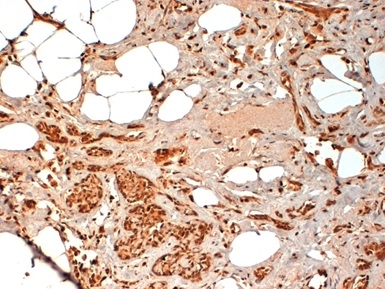

Periostin, Polyclonal Antibody (Cat# AAA19149)